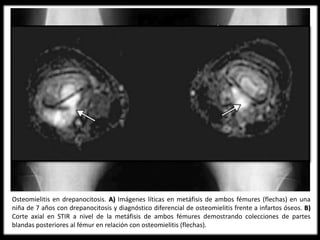

Osteomielitis en drepanocitosis. A) Imágenes líticas en metáfisis de ambos fémures (flechas) en una

niña de 7 años con drepanocitosis y diagnóstico diferencial de osteomielitis frente a infartos óseos. B)

Corte axial en STIR a nivel de la metáfisis de ambos fémures demostrando colecciones de partes

blandas posteriores al fémur en relación con osteomielitis (flechas).